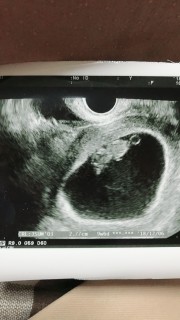

8w6dかと思っていたけど9w3dで予定日算出されました。4日ワープしました。GS45.2mmCRLは23mm。2w前はGS20.7mmCRL8.3mmでした。GSは倍に、CRLは3倍弱に成長していました。